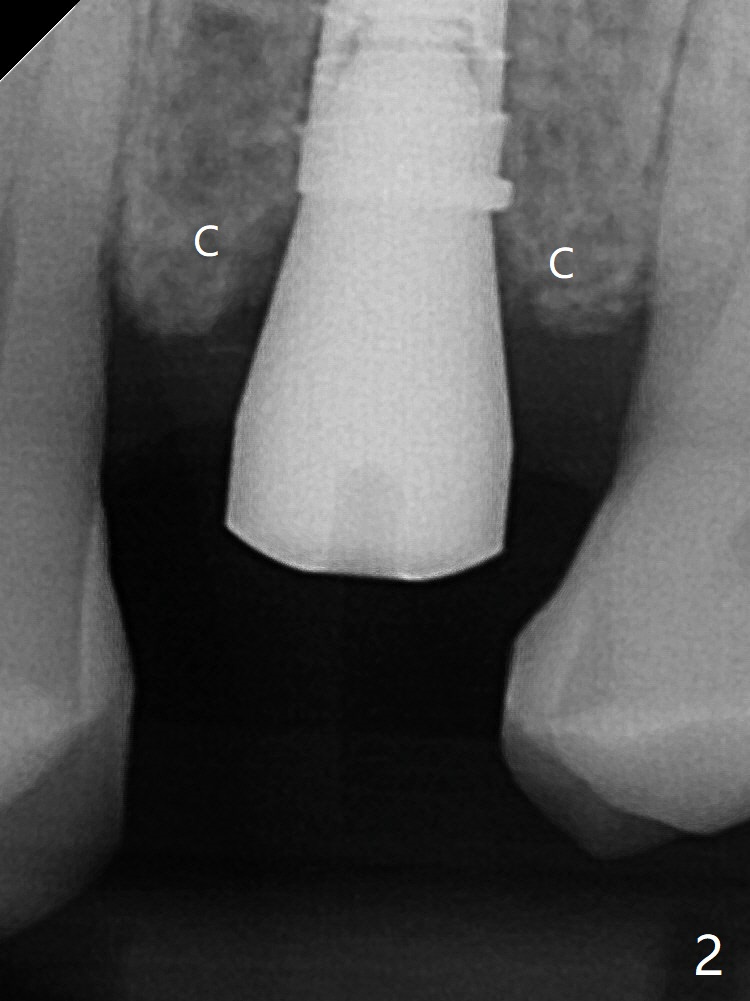

When a 4x11 mm FC is placed to the depth at #13, the palatal crestal bone is indistinct on probing. The implant is then placed ~ 1 mm deeper. To avoid contact between the future abutments and the mesiobucco-distal crest, a 5.5 mm profile drill is used. It appears that a 5x4 mm healing abutment has clearance from the crest (Fig.1,2 C). Immediate postop CT 3 D palatal view shows slight possible implant (Fig.3 I) thread exposure disto-palatal. To avoid this situation, the implant should have been designed more buccal (Fig.4 coronal section) because of the preexisting palatal defect (Fig.5,6) with low bone density palatocoronally (Fig.7). CT should have been taken prior to extraction. PRF or GEM21S should have been used. The patient will return for restoration (probably progressive loading) 3 months postop. In fact a pair abutment is placed 6 months postop (due to coronavirus, Fig.8). There is crestal bone palatal to the implant 6.5 months postop (Fig.9).